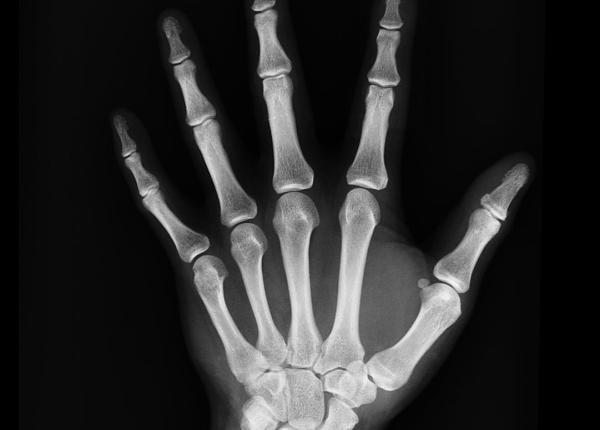

Cunoscutul medic-scriitor Vasi Rădulescu mai demontează un mit, cel al remediilor naturiste sau rapide pentru monturi. Un singur lucru funcționează cu adevărat, spune...